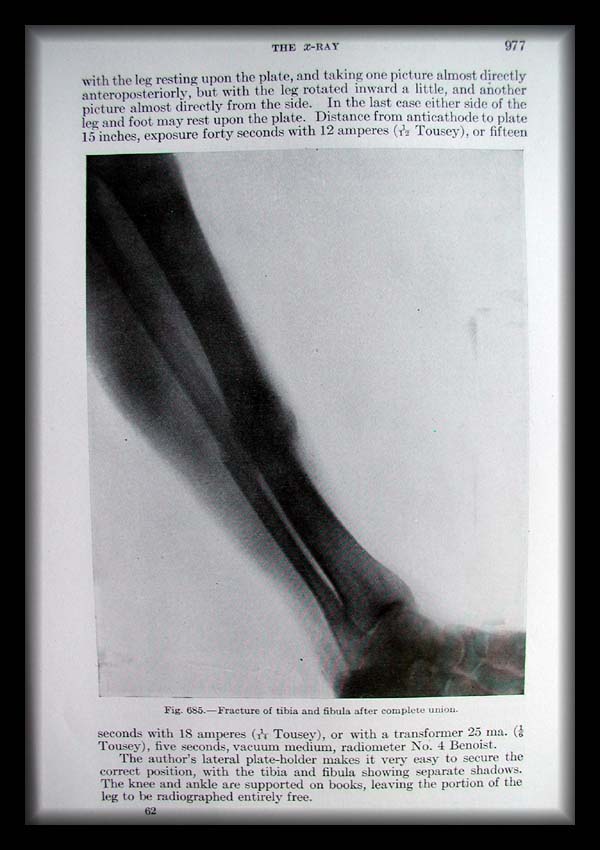

Previous Next